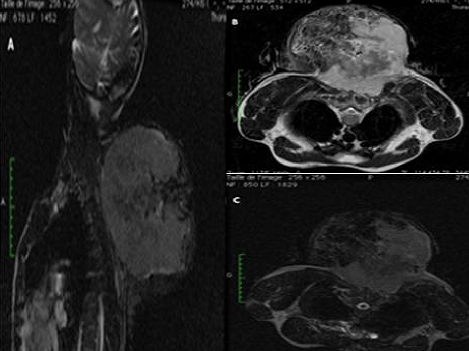

Le sarcome d'Ewing des parties molles est une tumeur mésenchymateuse rare, de mauvais pronostic, qui doit bénéficier d'un diagnostic précoce, afin d'offrir les meilleures chances de survie. Devant l'absence de signes cliniques et radiologiques spécifiques, il semble nécessaire de l'inclure comme diagnostic différentiel devant toute tumeur primitive des parties molles et y penser même devant des localisations inhabituelles. La localisation cervicale est inhabituelle et ne représente que 7% des sarcomes d'Ewing des parties molles. L'imagerie, en particulier l'IRM, permet un bilan lésionnel et d'extensions exhaustives et un suivi thérapeutique. Il s'agit d'un patient âgé de 35 ans, sans antécédent particulier, qui présentait depuis 7 mois une tuméfaction postérieure au niveau de la charnière cervico-dorsale, ayant augmentée progressivement de volume, non douloureuse, qui évoluait dans contexte d'altération de l'état général et d'amaigrissement important. L'examen clinique mettait en évidence une énorme masse ferme, insensible, fixe par rapport au plan superficiel, mesurant environ 174x197x165 mm, non soufflante, sans signes inflammatoires ou circulation veineuse collatérale en regard ni adénopathies locorégionales. Le patient a bénéficié d'une IRM objectivant un volumineux processus lésionnel pariétal de la région cervico-dorsale de signal hétérogène en T2 et T2 FAT SAT (A, B, C). Ce processus tumoral infiltrait le plan musculaire superficiel et profond de la région cervico-dorsale arrivant jusqu'au niveau des muscles para vertébraux à gauche sans signes d'extension rachidienne ni endocanalaire. L'examen anatomapathologique avec étude immuno-histochimique a permis de confirmer le diagnostic de sarcome d'Ewing des parties molles.